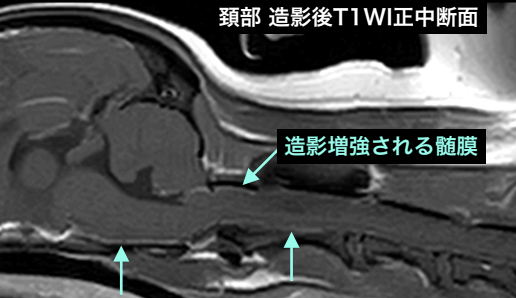

頚髄髄膜炎と診断した症例 炎症によって髄膜が肥厚し血流増加するため髄膜が明瞭に造影される